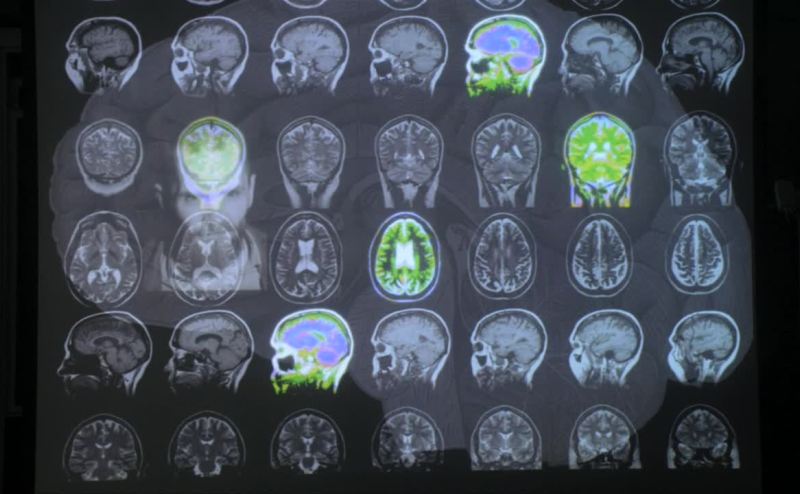

These 5 were the brains of serial killers

Some of whom you know.

In studies such as these

One looks at the biological factors...

That is the genetics and also the brain pathology.

The 5 brains we identified

All had damage to the orbital cortex

Which is right above the eyes.

Now high-risk allele of the monoamine oxidase A

The MAOA gene

May also be present in these people